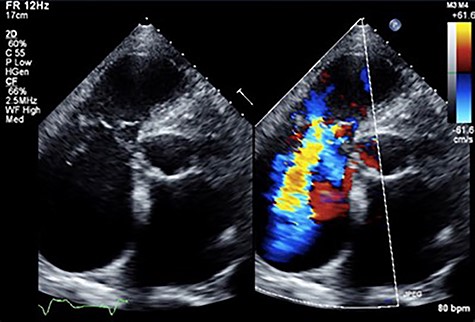

An 81-year-old male presenting with a PM pocket-associated infection was referred to our institution. Twelve years prior, a conventional PM was implanted for bradycardia and atrial fibrillation. A pocket infection was noted after the device generator was changed one month prior. We performed a complete pacing system extraction, but during explantation of a transvenous lead via simple traction, myocardial tissue adherent to the lead was concomitantly removed. Subsequently, the patient developed ventricular fibrillation. An immediate transthoracic direct-current cardioversion resulted in successful defibrillation. Postoperative transthoracic echocardiography (TTE) revealed tricuspid valve destruction and severe regurgitation (Fig. 1). A hasty surgical repair of the tricuspid valve or implantation of new transvenous leads seemed undesirable at the time because of ongoing active endocarditis. In addition, with the hope that the patient could tolerate severe TR as he had moderate TR preoperatively secondary to his PM lead, we considered a leadless transcatheter pacing system, Micra implantation without tricuspid valve repair. Micra implantation procedures went well, and after sufficient antibacterial therapy, the patient was discharged stable (Fig. 2A).